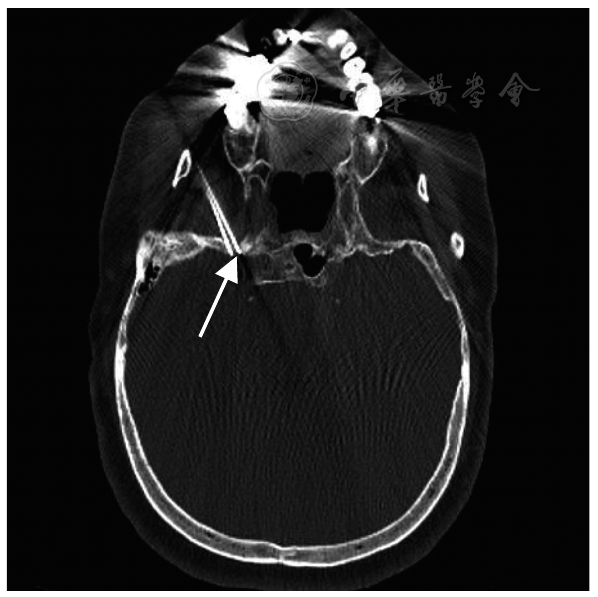

图1 GPN合并TN患者的三叉神经MRI影像资料未见三叉神经有血管压迫征象(箭头所示);GPN:舌咽神经痛;TN:三叉神经痛

Fig.1 MRI data of the trigeminal nerve in patients with GPN combined with TN